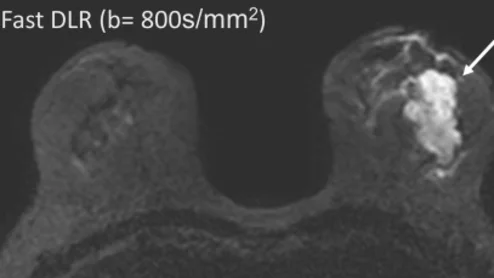

AI detects subtle changes in images over time.

The Learning-based Inference of Longitudinal imAge Changes, or LILAC, system harnesses machine learning to review medical images that have been collected over a prolonged period.